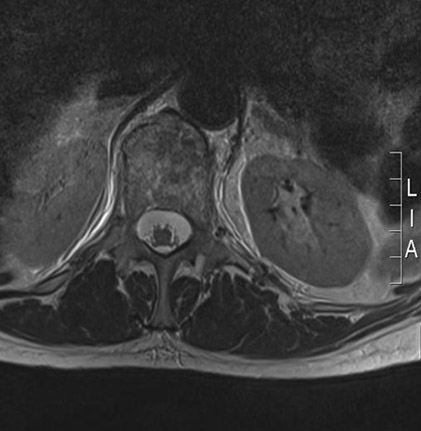

MRI lumbar spine: axial view (T2-weighted sequence) showing an osteoporotic fracture of the T12 vertebral body

From the personal collection of Dr B. Nurboja and Mr D. Choi